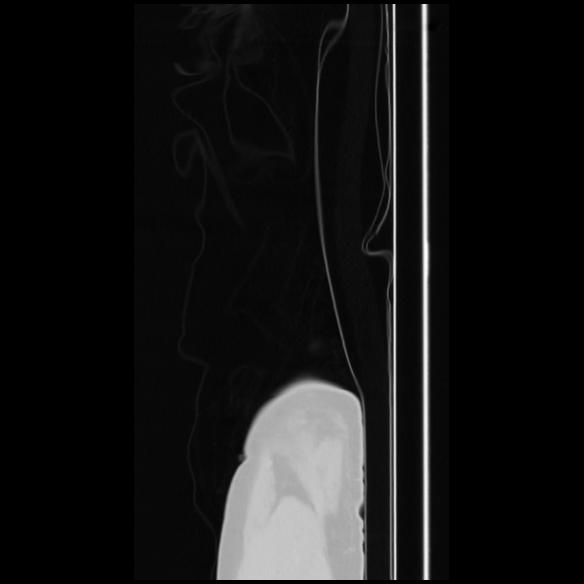

7 CUERPO,CE,Sagittal,3.000,CUERPO,Sagittal,